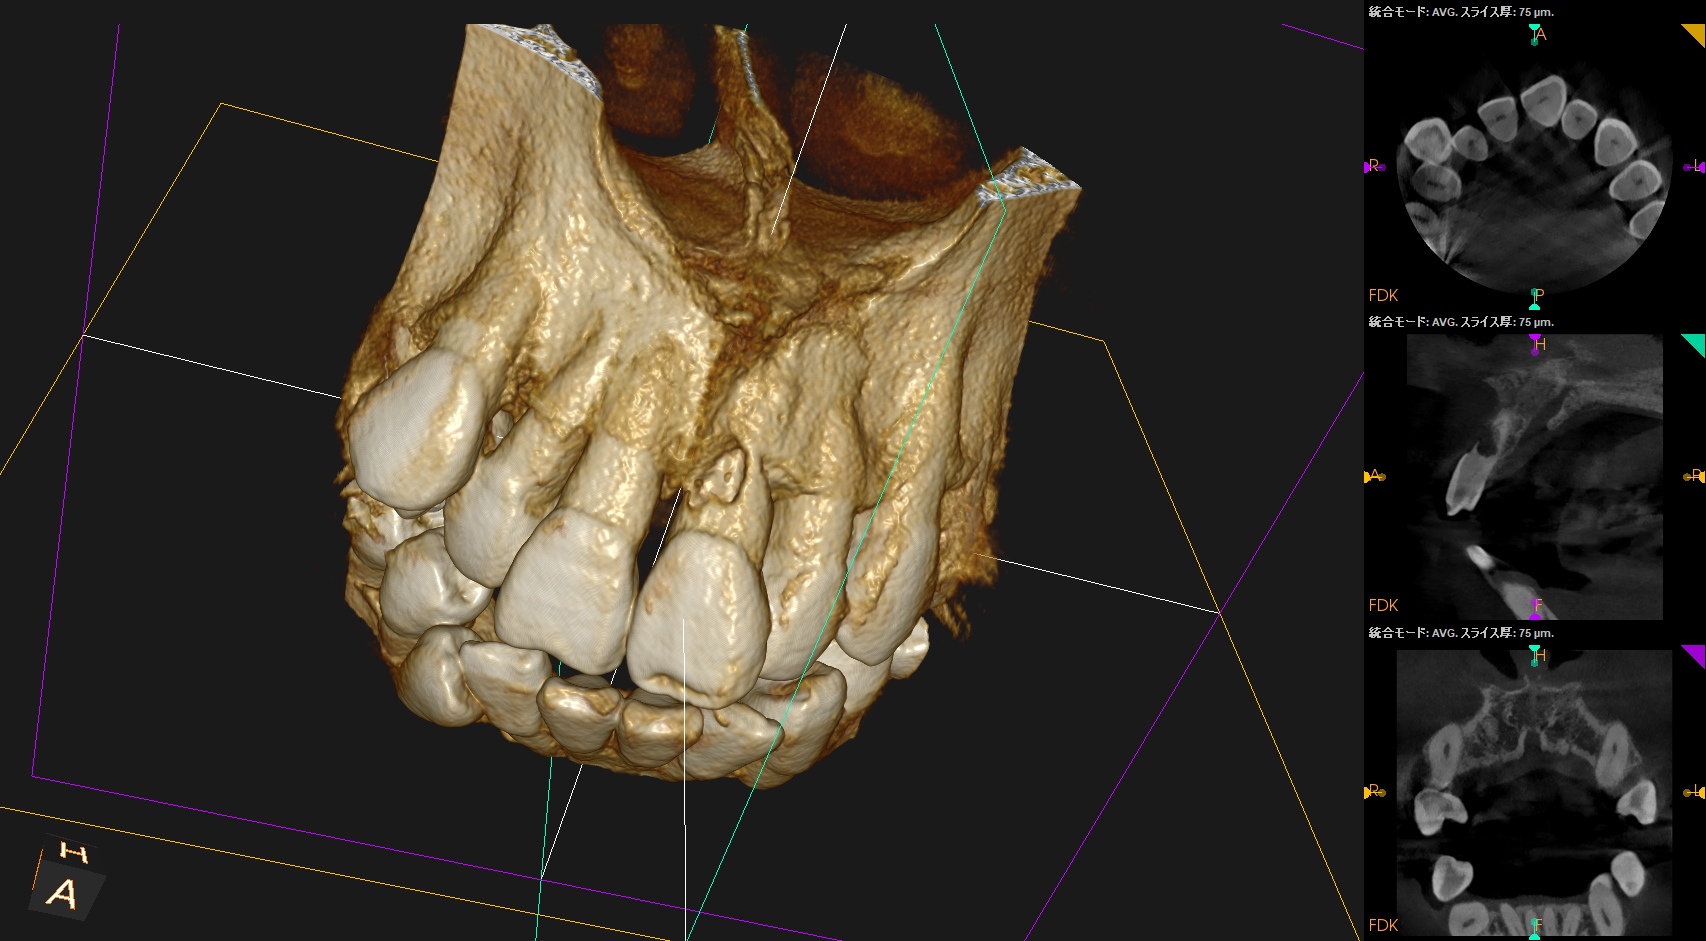

#9の頬側に大きな穴がある。が、根尖病変はない。

根管治療して、支台築造して、外部吸収のRepairだが、

根管治療すると外部吸収部位が薄皮一枚で交通しているのがネック

外部吸収のRepairを行うときに根管までも封鎖してしまう可能性があるのでそこをどう処理するか?が重要だが、このCBCTの絵からはラバーダム防湿しての根管治療はほぼ無理である。